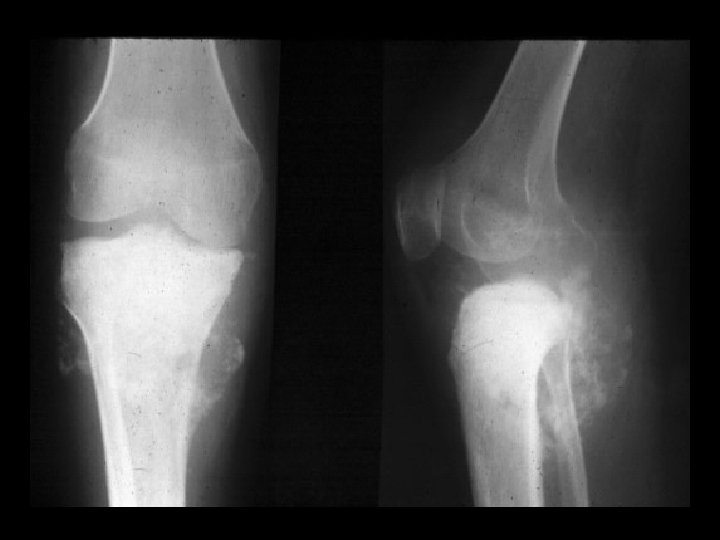

Giant cell tumor • Findings: – End of bone lucent and expansile lesion with a narrow zone of transition – No periosteal reaction or soft tissue mass • ddx: – ABC – metastasis – chondroblastoma

Giant cell tumor • Findings: – End of bone, eccentric, lucent lesion with narrow zone of transition but no sclerotic margin • ddx: – Fibrous dysplasia – ABC – Chondroblastoma